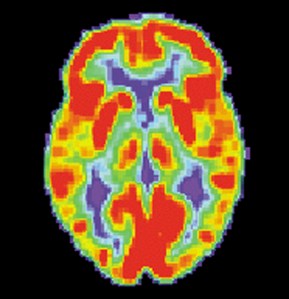

Research published over the last several years shows both physical and behavioral indicators of likely criminal activity. Scans done on a group of men and women with antisocial personality disorder, a trait that has shown some correlation with criminal conduct, have revealed reductions in two areas of the brain’s frontal lobe and in the amygdala, which is the part of the brain that controls emotion. A long-term study that followed young children into adulthood showed that those who displayed a lack of fear and a callous or detached attitude when kids more often earned a criminal record as they grew into teens and young adults.